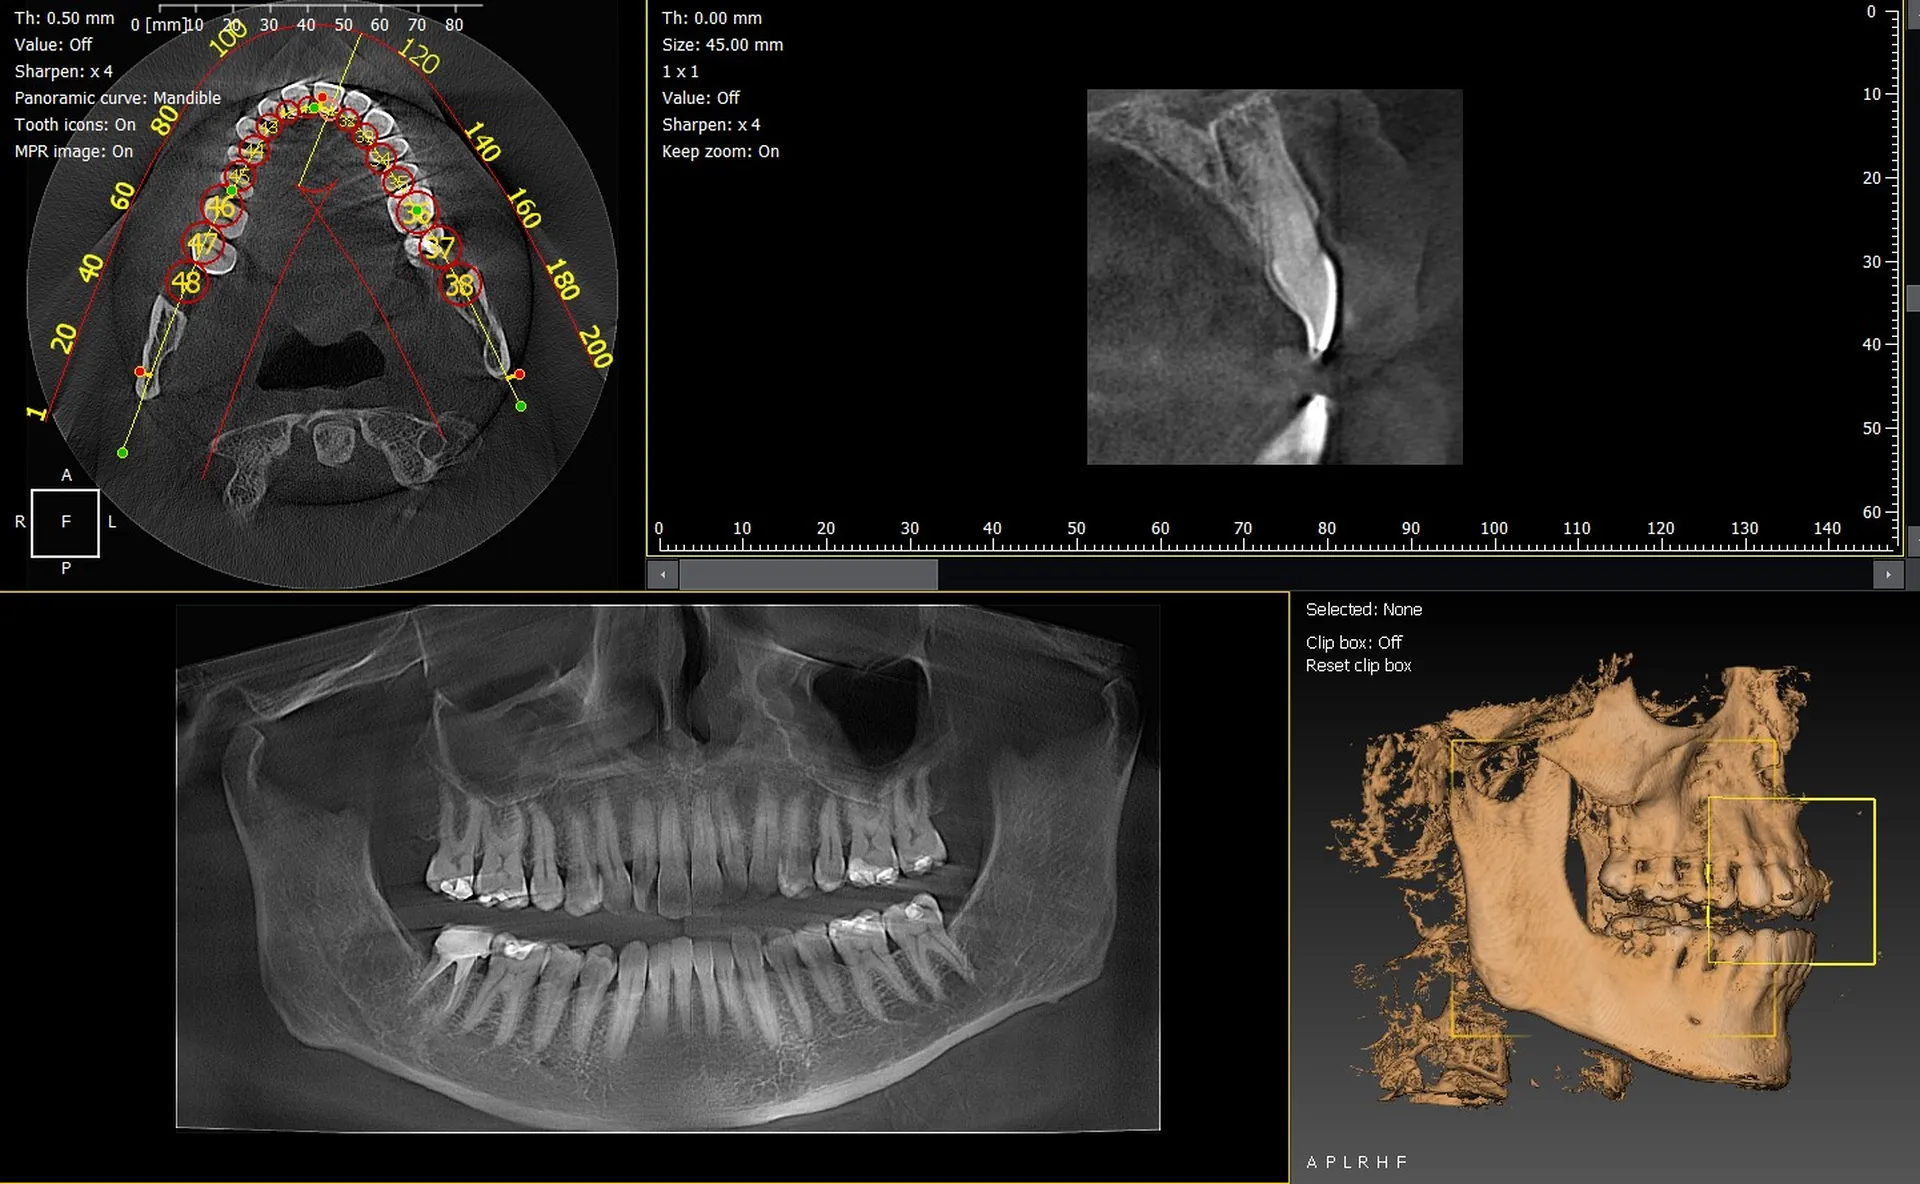

Les cabinets dentaires de Cavaillon et du département du Vaucluse (84) modernisent leur plateau technique grâce à des solutions d’imagerie 3D performantes et fiables. Les panoramiques CBCT 3D VistaVox de Dürr Dental et Owandy I-Max 3D figurent parmi les équipements les plus avancés, offrant une qualité d’image exceptionnelle et un diagnostic précis pour toutes les spécialités dentaires.

VistaVox 3D : précision et champ d’exploration optimisé

Le VistaVox 3D se distingue par :

• un champ d’exploration adapté à la forme réelle de l’arcade,

• une haute résolution idéale pour implantologie et endodontie,

• une réduction de dose parfaitement maîtrisée,

• un positionnement rapide du patient.

Owandy I-Max : compact, intuitif et performant

L’Owandy I-Max 3D est reconnu pour :

• son design mural ultra-compact,

• ses protocoles 2D/3D rapides et efficaces,

• son excellente qualité d’image,

• sa simplicité d’utilisation.